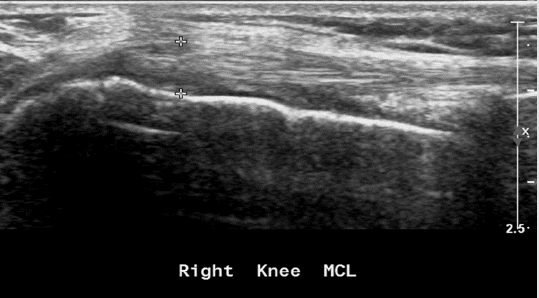

Figure 12: Pellegrini Stieda disease - thickening with calcifications at the insertion of the ligament to the Femur, a manifestation of chronic changes because of old partial tear.